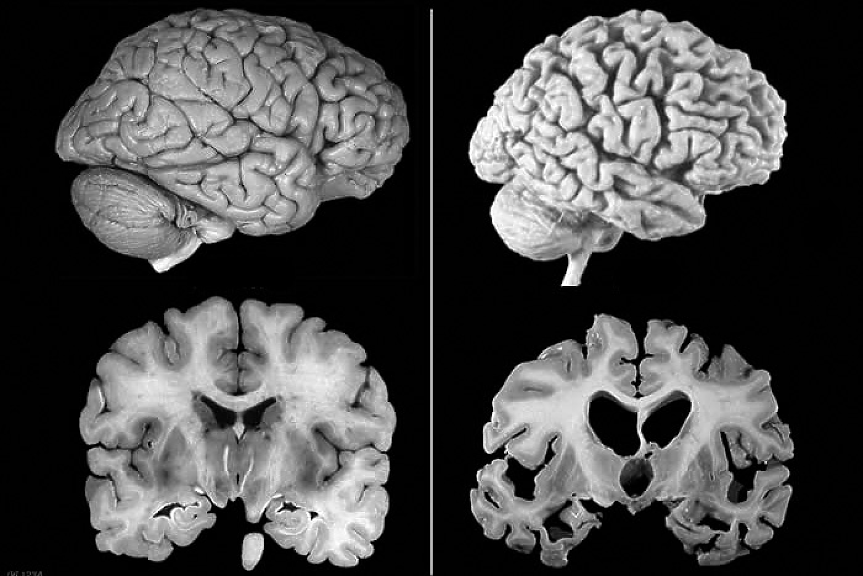

Търсенето на работещо лекарство срещу Алцхаймер от години е нещо като търсенето на Светия Граал за глобалната фармацевтика. Над 50 милиона души в света са засегнати от коварната болест, която убива нервните клетки в мозъка.

Целта на фармацевтите е да намерят лек, който поне спира или забавя развитието на болестта.